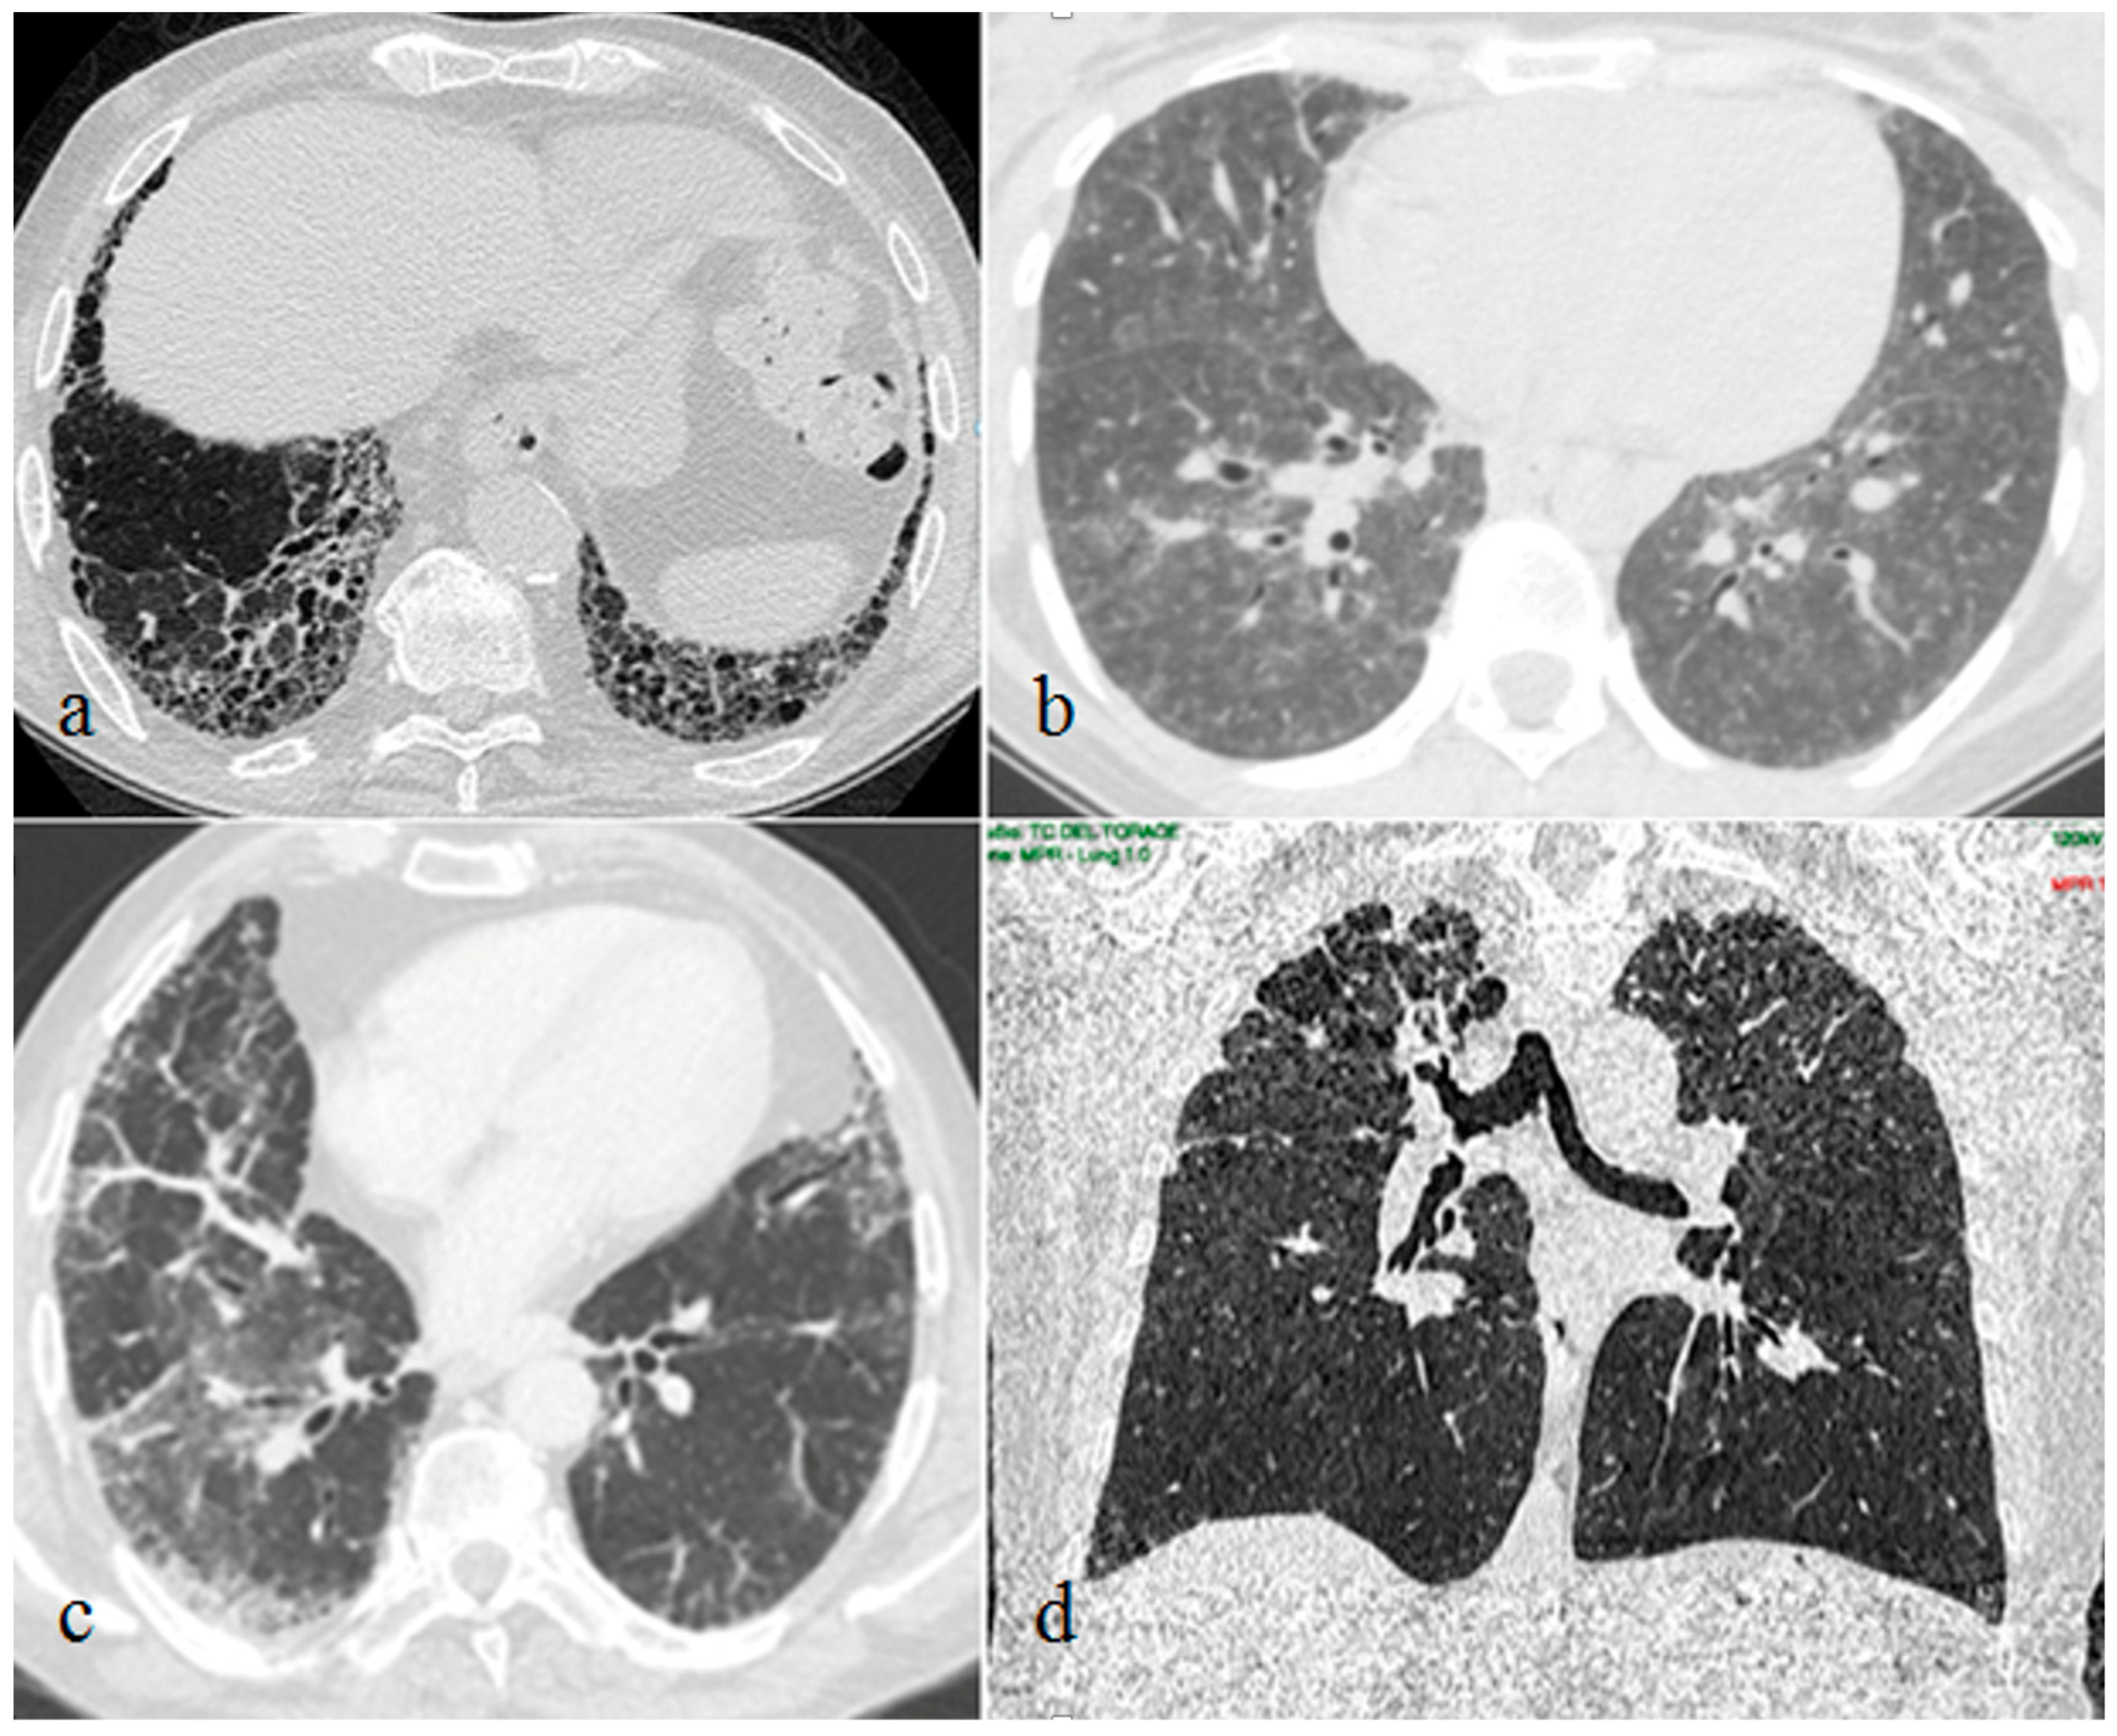

Furthermore, we reported the typical CT findings of the ILDs detected in our patients. UIP radiological features were subpleural and basal predominant honeycombing or reticulation with peripheral traction bronchiolectasis. NSIP was mainly characterized by bilateral patchy areas of ground-glass attenuation with basilar distribution and relative immediate subpleural sparing. HP typical radiological findings were diffuse with possible basal sparing ill-defined centrilobular nodules and/or air trapping associated with ground glass opacities and/or mosaic attenuation with or without fibrosis. PPFE CT images showed upper lobes predominant pleural and subpleural thickening with a reticular pattern, with possible associated upper lobes volume reduction and traction bronchiectasis.

The 10 lung biopsies performed confirmed the diagnosis suspected by the corresponding chest CT patterns. Seven patients showed NSIP, one patient showed PPFE, one patient showed HP and one patient showed early UIP pattern (Figure 2).

Figure 2.

Interstitial lung disease patterns in patients with plaque psoriasis: usual interstitial pneumonia (a), hypersensitivity pneumonitis (b), nonspecific interstitial pneumonia (c), pleuropulmonary fibroelastosis (d).